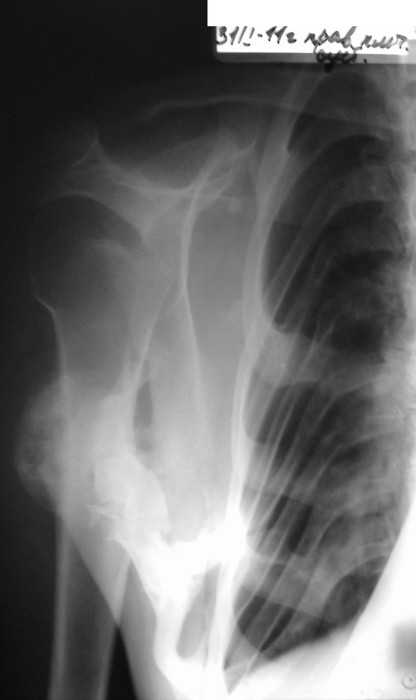

Жалобы: на нарушение функции верхних конечностей: невозможность движения в обеих правых плечевых и локтевых суставах; ограничение движений в шейном отделе позвоночника, наличие опухолевидных множественных образований на спине и пробам бедре.

Анамнез заболевания: со слов матери появлению множественных опухолевидных образований на спине предшествовал массаж воротниковой зоны в 4 года. Консультирован в Областной детской больнице и Областном онкодиспансере. В декабре 2010 г. после падения с велосипеда ушиб левый локтевой сустав, a в январе вторичное падение с велосипеда с ушибом правого локтевого сустава, после чего пациент отметил постепенное ухудшение функции обеих верхних конечностей вплоть до резкого ограничения объема движений в обеих плечевых и локтевых суставах.

Место болезни: при осмотре определяется - вынужденное положение верхних конечностей в плечевых и локтевых суставах, множественные опухолеподобные образования вдоль позвоночника и по наружной поверхности верхней трети левой бедренной кости округлой формы, с четкими контурами, неподвижные, безболезненные, каменистой плотности. приводяще-отводящая контрактура в обеих плечевых суставах, сгибательно-разгибательная контрактура в обеих локтевых суставах с сохранение про- и супинационных движений. Объем движений в пальцах кисти и лучезапястных суставах в полном объеме без ограничений, безболезненный.

Диагноз: врожденная аномалия развития шейного отдела позвоночника с резким нарушением функции в плечевых и локтевых суставах, множественных костно-хрящевые экзостозы, оссифицирующий миозит.

рентгенограммы

это fibrodysplasia ossificans progressiva, генетически обусловленная прогрессирующая метаплазия соединительной и мышечной ткани в костную. Лечится (вернее, тормозится) консервативно, после попыток оперативного лечения и после травм - прогрессирует.